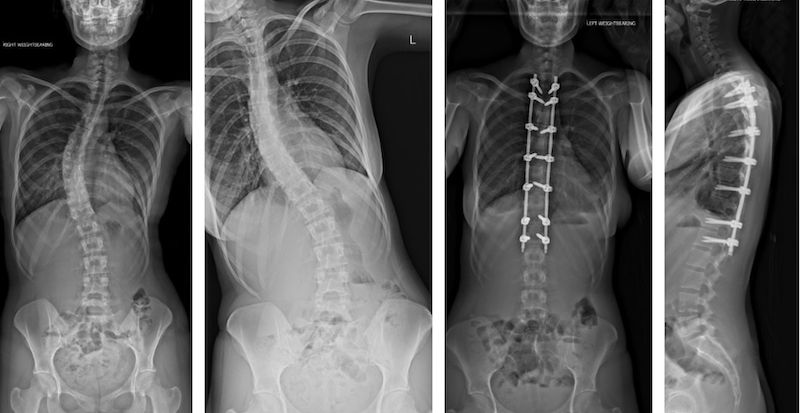

X-rays of Camille's own spine, pre- and post-surgery provided the inspiration for her designs

Camille was diagnosed with scoliosis in 2017, and surgery to correct the 40-degree curvature in her spine was booked for the start of 2020. But Covid put the brakes on that plan, and she was unable to have the operation until February – just months before her final project had to be completed.

Camille used imagery of her own body as inspiration for her designs.

“I had always found it slightly weird looking at MRI scans and X-rays of myself as I had slightly desensitised myself from it and didn’t look at the images and think ‘that’s me’,” she said. “Creating my textile prints has made me appreciate my body and I can stop and look back at my work and think that pattern there is my rib cage and not a lot of people are able to do that.